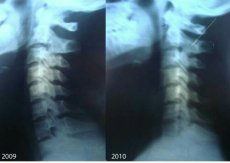

Лучанка Валентина Горайчук потребує допомоги. Дівчина збирає кошти, аби поїхати на діагностику до Києва. Бо у Луцьку, за її словами, лікарі допомогти їй не можуть.

Без корсета шия не тримається! А в ньому стає нестерпно.

В мене є попередній діагноз професора вертебролога зі Львову, пов'язаний з динамічною патологією. М'язи шиї не слухаються. Хвороба не христоматійна, випадок мабуть одиничний. Я в розпачі. Пишіть, якщо хтось щось про таке чув або знає! Луцькі лікарі розводять руками, або не допомагають і діагноз не підтверджують. Всі, хто мене знає, дуже багато людей - можуть підтвердити, що я НЕ видумую і проблеми були ще в школі, в інституті рік не могла ходити, я лежала в лікарнях неодноразово», - пише дівчина.